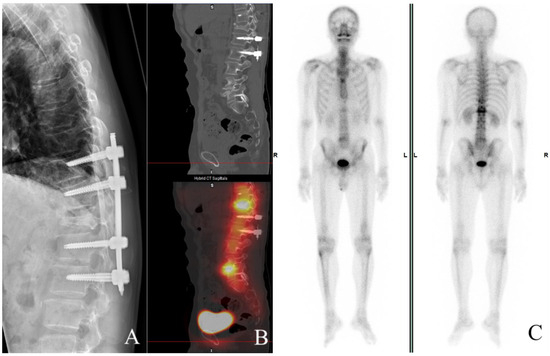

2.3. Surgery and Post-Operative Findings